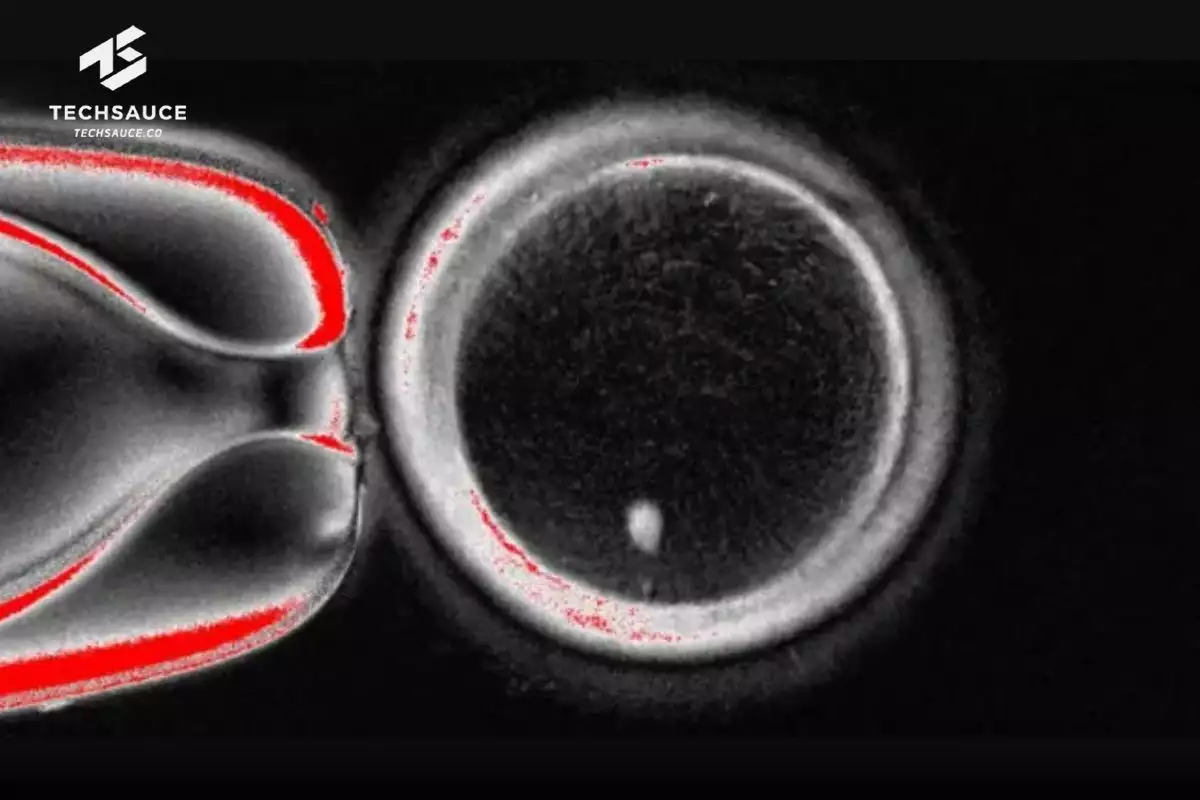

นักวิจัยสร้างไข่ขึ้นทั้งหมด 82 เซลล์ แล้วนำไปปฏิสนธิกับอสุจิด้วยวิธี IVF แต่มีเพียงราว 9% ที่พัฒนาเป็น blastocyst ซึ่งเป็นขั้นตอนตัวอ่อนตอนหลังไข่ปฏิสนธิ โดยเป็นกลุ่มเซลล์กลวงที่แบ่งตัวเร็ว และเป็นช่วงสำคัญที่ตัวอ่อนพร้อมฝังตัวในมดลูก

แม้ไข่บางเซลล์จะพัฒนาไปถึงขั้น blastocyst แล้ว แต่ก็ยังมีปัญหาเรื่องโครโมโซมอยู่ เช่น บางเซลล์มีโครโมโซมมากหรือน้อยเกินไปหรือบางตัวก็ขาดไป ทำให้ไข่พวกนี้ยังใช้ทำ IVF ไม่ได้ นักวิจัยเลยบอกว่าเทคนิคนี้ ยังไม่พร้อมใช้ ต้องทำการวิจัยต่ออีกก่อนถึงจะปลอดภัยและได้ผลจริง